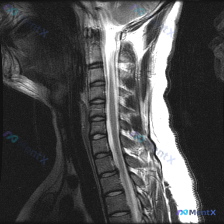

整理了一份颈椎影像资料,有点意思: - 最初的问题提了“脊柱侧弯”的观察方向 - 影像只有颈椎MRI T2加权矢状位 - 看图像细节,发现了几个比“侧弯”更直接的征象 大家先看看这份影像的结构化描述,第一反应会把哪个问题放在优先级最高的位置?